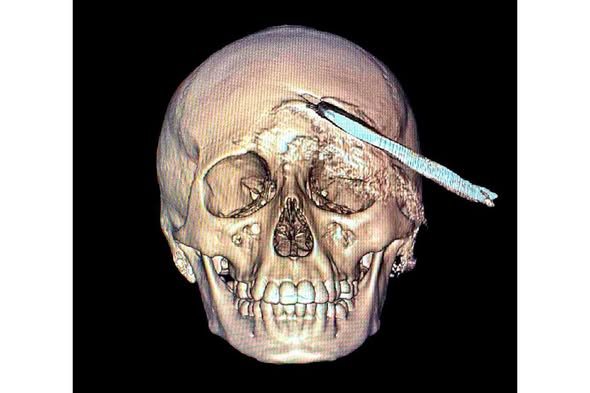

El joven de 15 años fue sometido a una intervención de cuatro horas, donde sin afectar tejido cerebral, le fue retirado un machete curvo.

Especialistas del HGR No. 1 afirman que este es el primer caso pediátrico que se atiende en el estado con esta clase de lesión.

Personal médico del IMSS Yucatán logró salvar la vida de un adolescente de 15 años que llegó con una herramienta agrícola INCRUSTADA en el cráneo. Tras ser trasladado de emergencia desde Acanceh, el paciente recibió atención en el Hospital General Regional No. 1, donde especialistas en neurocirugía, pediatría y terapia intensiva coordinaron una intervención de alta complejidad para retirar la coa metálica sin causar daño cerebral.

El procedimiento, liderado por el neurocirujano Luis Víctor Ornelas González, tuvo una duración aproximada de cuatro horas y requirió estudios de imagen avanzados, manejo antimicrobiano especializado y seguimiento continuo en terapia intensiva pediátrica.